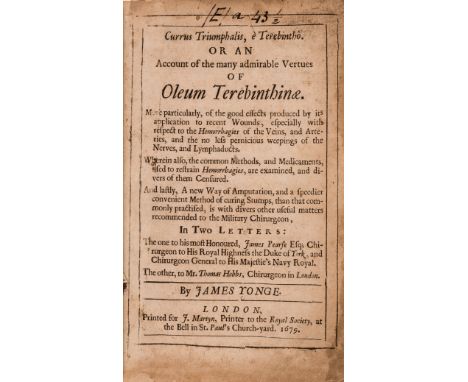

Yonge (James) Currus triumphalis, e Terebintho. Or an Account of the many admirable Vertues of Oleum Terebinthinae, first edition, old ink note to head of title, browned, a few minor marginal defects, modern bookplate of the orthopaedic surgeon/medical historian John R.Kirkup with his pencil notes to front pastedown, later calf, rubbed, rebacked, red morocco label, [Wing Y39], 8vo, J.Martyn, 1679.⁂ Concerning the use of oil of turpentine to suppress haemorrhage, and describing for the first time the use of a flap of tissue in amputations.